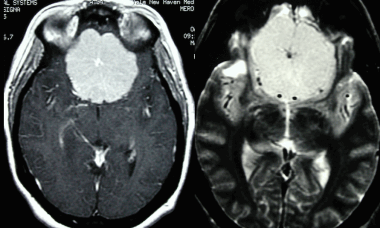

8. На рентгеновском снимке во фронтальной плоскости хорошо заметно кальцифицированное образование в области лобной пазухи. На снимке в латеральной проекции образование визуализируется кверху от решетчатой пластинки. Несмотря на то, что по результатам исследования можно заподозрить, обнаруженные признаки неспецифичны, и поэтому обнаруженное внутричерепное образование требует дообследования при помощи КТ.

Большинство рентгеновских снимков не отображают признаков наличия заболевания. Менингиомы типа en plaque характеризуются диффузным гиперостозом, чаще в области крыла клиновидной кости и птериона. Такие результаты исследования с большой долей вероятности свидетельствуют о наличии

болезни.